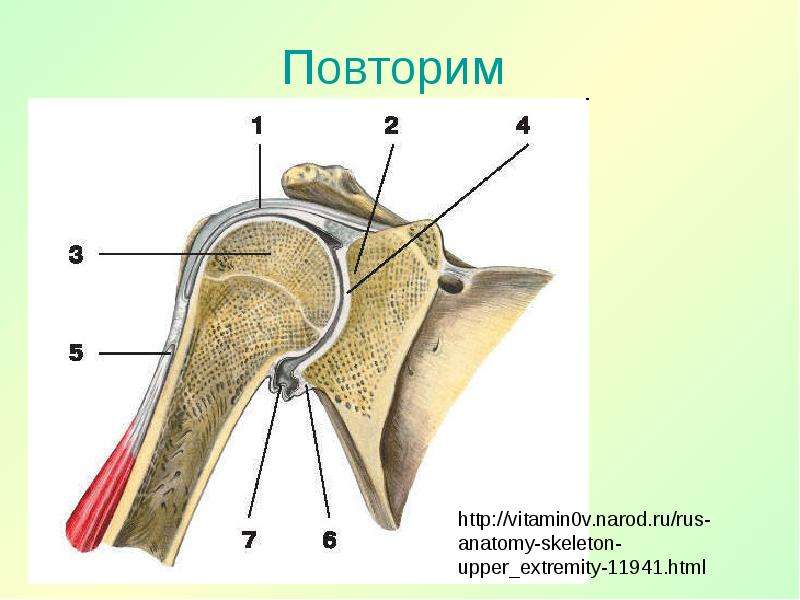

Рисунки Суставов: Анатомические Иллюстрации